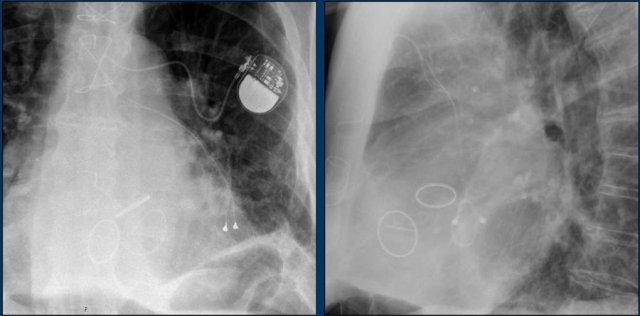

Các phát hiện bao gồm:

- Hai điện cực thượng tâm mạc kết nối với máy tạo nhịp

- ICD

- Hai điện cực đến mỏm thất phải

- Một điện cực chứa hai cuộn sốc điện

- Van ba lá (mũi tên)

- Van hai lá

Bệnh nhân này đã được sửa chữa ba van:

- Van ba lá

- Van động mạch chủ

Có máy tạo nhịp tim với điện cực thượng tâm mạc.

Phương án này được lựa chọn vì người ta cho rằng điện cực đặt theo đường thông thường vào thất phải sẽ ảnh hưởng quá nhiều đến chức năng của van ba lá nhân tạo.

Mũi tên trắng chỉ vào van động mạch chủ.

Mũi tên vàng chỉ vào van hai lá.